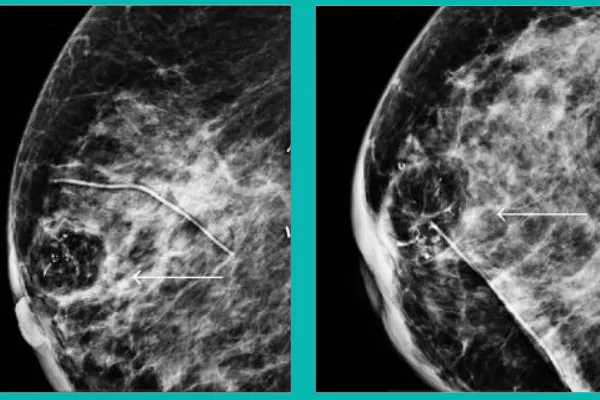

چرا ممکن است بعد از جراحی، تصویر مشکوک مانند BIRADS 4 دیده شود؟

این بخش برای بیماران بسیار مهم است.

بعد از جراحی کوچک کردن سینه:

- ممکن است بخشی از بافت چربی دچار فتنکروز (Nipple Fat Necrosis) شود.

- فتنکروز یعنی بخشی از چربی در اثر قطع خونرسانی یا فشار در فرآیند جراحی سفت و سفتتر میشود.

این بافت در ماموگرافی یا سونوگرافی ممکن است:

- شبیه توده

- شبیه کلسیفیکاسیون

- یا حتی شبیه بافت مشکوک به بدخیمی

به نظر برسد.

اما این یک بدخیمی نیست. فتنکروز یک عارضه بیخطر و بسیار رایج بعد از جراحی و حتی بعد از ضربه ساده به سینه است.

چگونه تشخیص داده میشود که توده، فتنکروز است و نه سرطان؟

برای تشخیص قطعی و جلوگیری از نگرانی:

| روش | دلیل استفاده |

|---|---|

| نمونهبرداری سوزنی (Core Needle Biopsy) | تشخیص قطعی و بدون نیاز به جراحی بزرگ |

| MRI سینه | شفافسازی موارد مشکوک در mammography یا سونوگرافی |

بنابراین:

مشاهده «BIRADS 4» بعد از جراحی به معنی سرطان نیست.

بلکه یعنی باید بررسی دقیق انجام شود و در بسیاری موارد، نتیجه نهایی فتنکروز و بافت اسکار است، نه تومور.

آمار مهم:

بر اساس بررسیهای کلینیکهای جراحی پلاستیک و مراکز تصویربرداری:

- در بیمارانی که سابقه جراحی کوچک کردن سینه دارند، بیش از 70٪ موارد BIRADS 4 در نهایت فتنکروز تشخیص داده میشود.

- بروز سرطان واقعی در این گروه بسیار کم گزارش شده است.

این یعنی:

نگرانی بیش از حد بعد از خواندن گزارش تصویربرداری درست نیست.